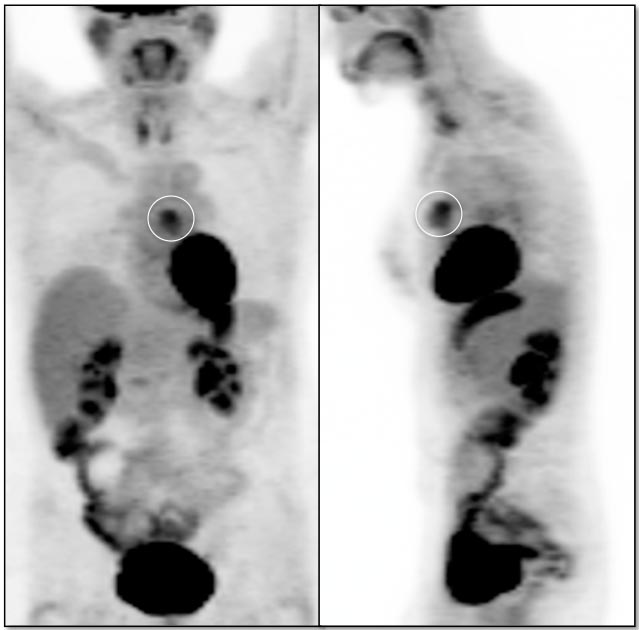

- Don’t Miss the Hidden Nod

- Reporting Language